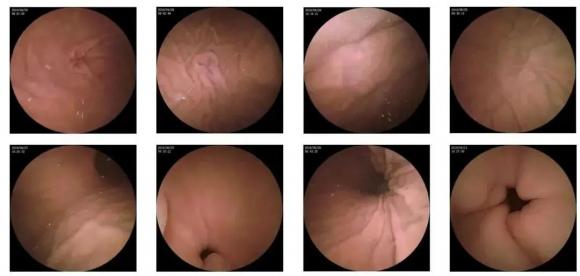

10—15分鐘即可完成賁門、胃底、胃體、胃角、胃竇、幽門等解剖部位觀察,讓胃部檢查更高效。更為重要的是,檢查全程不痛、沒創(chuàng)、無麻醉,避免了傳統(tǒng)插管胃鏡帶來的生理痛苦。

二、高清圖像,精確診斷

膠囊機器人的專利三鏡片鏡頭,可深入觀察0.04毫米微小單位,每秒可拍高達(dá)4張高清醫(yī)學(xué)照片。

醫(yī)生通過智能閱片系統(tǒng),可自動對海量圖像識別過濾,智能篩選,能有效提升醫(yī)生檢查及閱片效率。

任何細(xì)微的胃部病變,如胃潰瘍、胃出血、息肉等都無所遁形,盡在磁控膠囊式內(nèi)窺鏡系統(tǒng)的掌握之中。